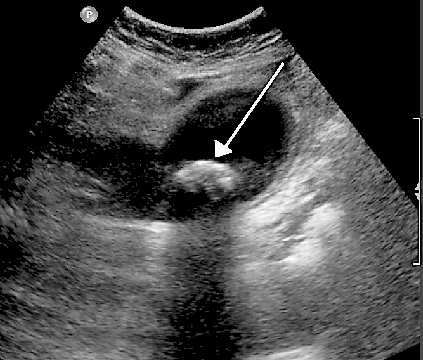

Another example is that when ultrasound travels though bile in a gallbladder it will echo back strongly if it hits a solid gallstone - as in the ultrasound image below. The arrow points to a gallstone in the gallbladder.

Gallstone ultrasound image

By James Heilman (Own work), via Wikimedia Commons